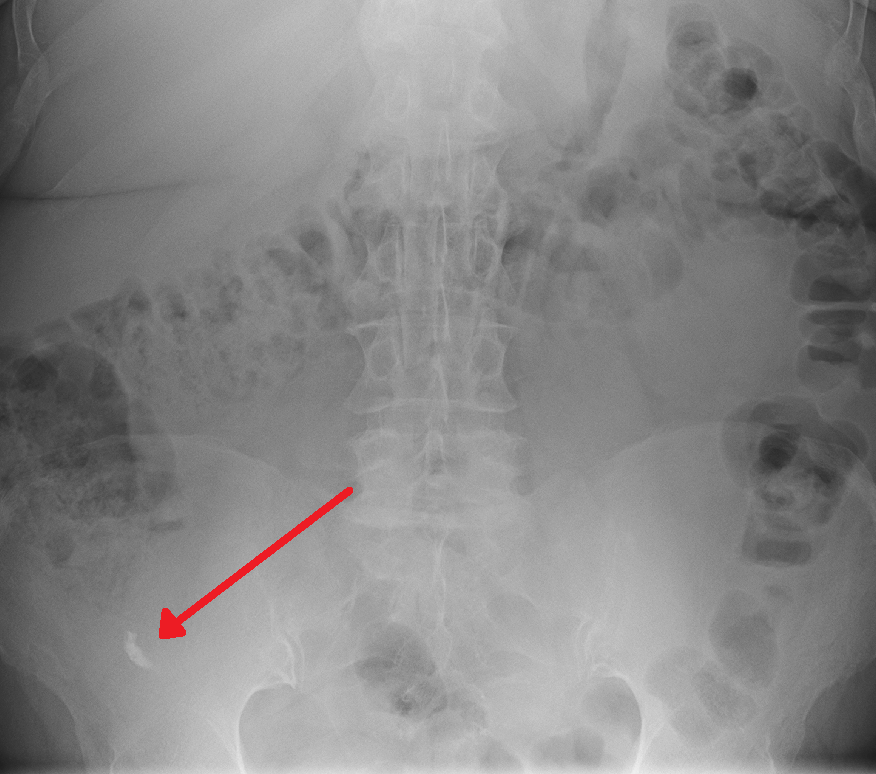

일반 복부 방사선 촬영(PAR)은 충수염 진단에 유용하지 않으며, 요관 결석, 소장 폐쇄, 천공성 궤양 감별에 제한적으로 사용된다.[69][70][71] 불투과성 분변결석은 5% 미만에서 확인된다.[48] 바륨 관장은 효과가 없는 것으로 입증되었다.[71]